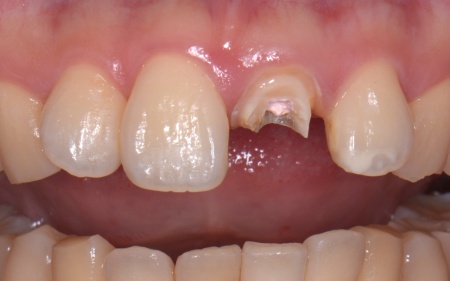

| 相談内容 | 「食事中に左上の前歯が折れてしまった」とご相談いただきました。 |

| カウンセリング | お口の中を拝見したところ、左上の前歯が大きく折れて被せ物を支える土台ごと外れていました。 レントゲン検査で確認した結果、歯の根自体には問題がなく炎症も見られなかったため、適切な治療を行えば歯を残せる状態であることが判明しました。 このまま放置した場合、残った歯根に細菌が入り込んで炎症を起こしたり、隣の歯に余計な負担がかかったりする可能性があります。 以上のことから、折れた歯を補う治療が必要と診断しました。 |